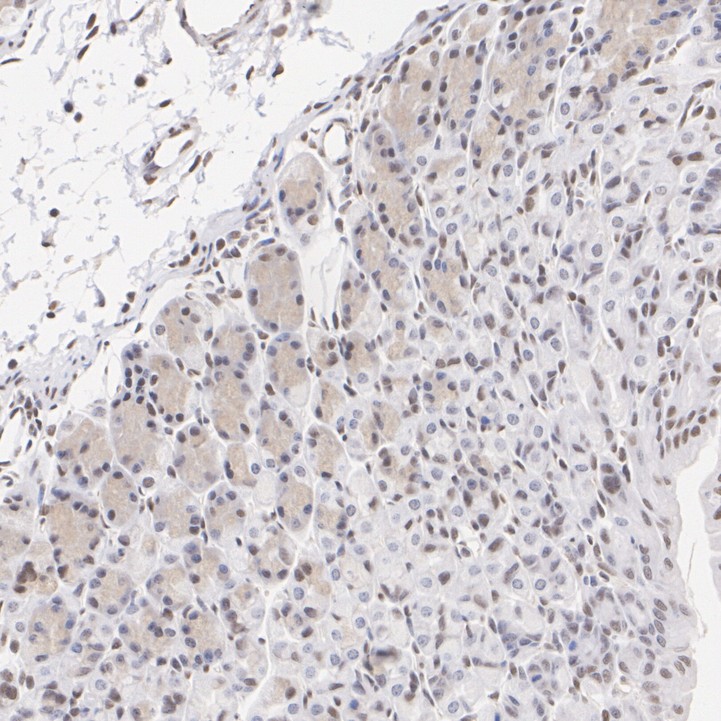

Immunohistochemical analysis of paraffin-embedded human breast carcinoma tissue with Rabbit anti-TAZ / WWTR1 antibody (HA723765) at 1/200 dilution.

The section was pre-treated using heat mediated antigen retrieval with Tris-EDTA buffer (pH 9.0) for 20 minutes. The tissues were blocked in 1% BSA for 20 minutes at room temperature, washed with ddH2O and PBS, and then probed with the primary antibody (HA723765) at 1/200 dilution for 1 hour at room temperature. The detection was performed using an HRP conjugated compact polymer system. DAB was used as the chromogen. Tissues were counterstained with hematoxylin and mounted with DPX.